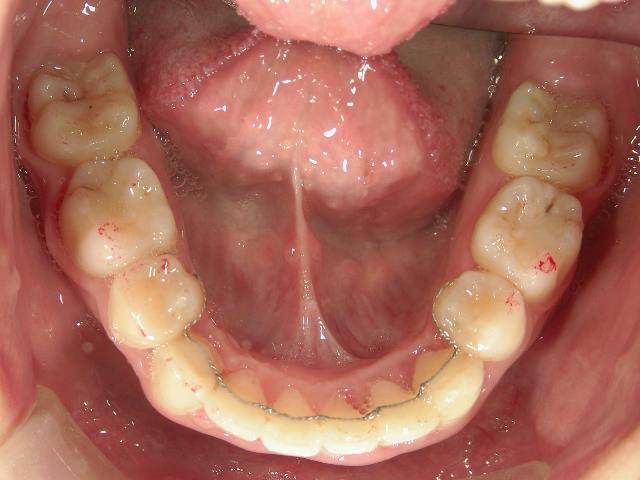

矯正歯科 治療後

矯正_灰色.pngno.18_2196_治療後_上.jpg矯正_灰色.png

矯正_灰色.pngno.18_2196_治療後_下.jpg矯正_灰色.png